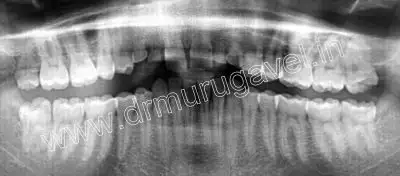

Radiographic examination

OPG shows retained deciduous tooth in relation to 12,13,22,23 region.. Sufficient bone height and width was present in relation to 12,13,22 and 23 region for placing basal implants..